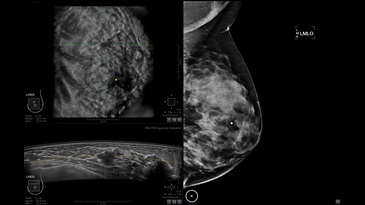

GE INVENIA ABUS – это современный УЗИ аппарат, который создан для точной и эффективной диагностики сканирования с высокой плотностью молочных желез. Выявляемость патологий раковых и предраковых стадий заболевания составляет 55%, что в конечном счете позволяет ставить врачу точные и своевременные диагнозы. Традиционные методы использования маммографии не показывают такой выявляемости, ограничиваясь лишь 3-38%.

УЗИ-аппарат GE INVENIA ABUS позволяет проводить максимально операторонезависимые процедуры, что значительно снижает риск неправильной постановки диагноза и сопутствующие издержки на обработку информации. Система готовит отчет в течение 3-х минут после сканирования, это безусловное преимущество по сравнению с обычным УЗИ сканером.

Данное устройство классифицируется, как стационарное, используемое в многопрофильных клиниках, женских консультациях, медицинских центрах. Вес без учета дополнительного оборудования составляет 105 кг. Удобная колесная база позволяет оперативно маневрировать в ограниченных пространствах, в том числе передвигать устройство в коридорах клиники. Большой 17-ти дюймовый монитор с широкими углами обзора выводит максимально качественную картинку в формате Full HD.

• Сенсорный монитор с диагональю 17”

• Встроенный сверхширокий вогнутый датчик C15-6XW: диапазон частот: 4 - 15 МГц; длина апертуры: 15,3 см; длина сканируемого участка: 16,9 см; количество элементов: 768